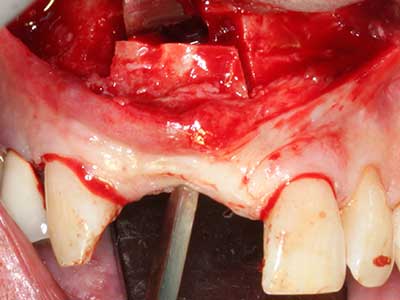

Knochengewebe ist nicht nur rein mineralisch, sondern auch in wesentlichen Anteilen aus Kollagenfasern aufgebaut. Dies gewährleistet neben einer guten Druckfestigkeit eine gewisse Flexibilität, welche für die Durchführung von Augmentationen genutzt werden kann. Bei der klassischen Expansionsplastik im Sinne eines Bone Splittings wird der atrophierte Kieferkamm in seiner Längsachse gespalten und nach Erreichen einer ausreichenden Osteotomietiefe vorsichtig aufgedehnt (Abb. 13-16), idealerweise ohne den Kiefer wesentlich zu deperiostieren (Brugnami, Caiazzo et al. 2014, Stricker, Fleiner et al. 2014). Bewährt haben sich Schrauben- und Plattensysteme mit zunehmender Expansionsdistanz, um die beiden Knochenlamellen unterhalb der Bruchschwelle voneinander zu distanzieren. In der Regel werden Restknochenbreiten von mindestens 3-4 mm gefordert (Chiapasco, Zaniboni et al. 2006), um eine ausreichende Flexibilität und knöcherne Bedeckung der einzubringenden Implantate zu gewährleisten. Ggf. kann eine ein- oder beidseitige vertikale Entlastungsosteotomie die Flexibilität verbessern. Als Alternative zur klassischen Technik wurde eine Kombination mit weiteren augmentativen Techniken vor allem auf der bukkalen Seite beschrieben.

Mittels Piezosägen erfolgt die Anlage des Splittings besonders schonend und ohne wesentliche Dimensionsverluste, so dass sich keine signifikanten Unterschiede von Implantaten im gesplitteten Kiefer im Vergleich zum nicht defizitären Alveolarkamm gezeigt haben (Chiapasco, Zaniboni et al. 2006, Danza, Guidi et al. 2009). Gerade beim lokal begrenzten und tiefen Splitting ist jedoch stets auf eine ausreichende Wasserkühlung zu achten, um thermische Belastungen in den apikalen Osteotomiebereichen zu vermeiden.